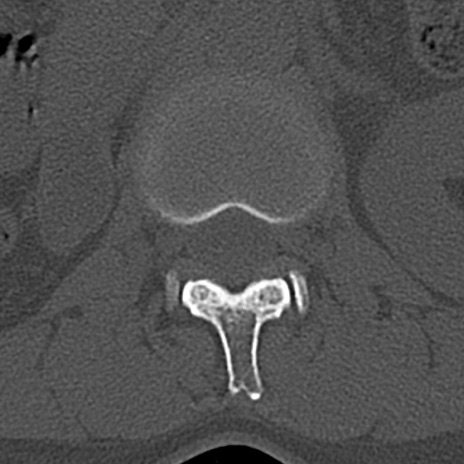

【整形】TIPS症例4 腰椎CT(横断像)

腰椎CT

横断像と矢状断像